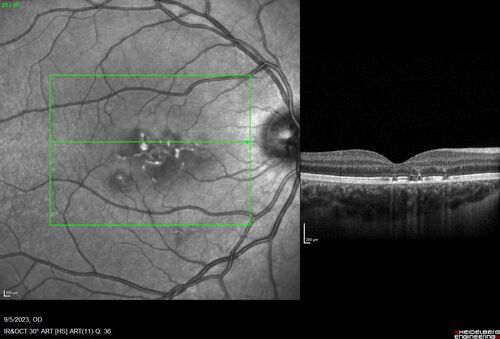

Laser pointer maculopathy

11 year old male When school started the patient noticed that he was having trouble reading and seeing out of both eyes. There are no retinal diseases in the family.

VA OD: sc20/25

VA OS: sc20/40

TP: OD:19 OS:18